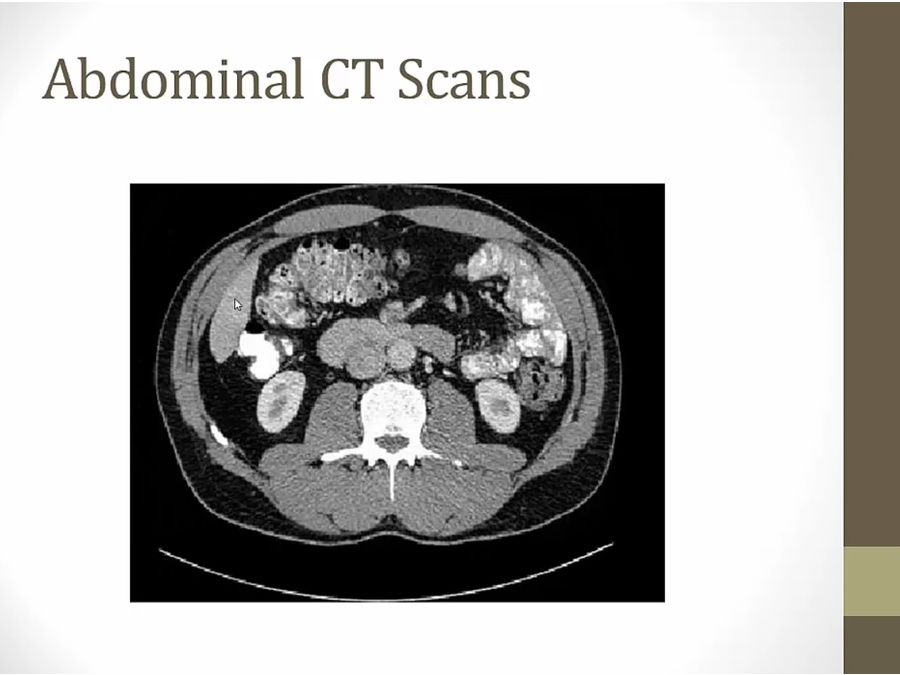

right:

liver: smaller

spleen: solid, no air

bottom: air, distal colon, rectum

next to bone: psoas and iliacus muscles

next to liver: stomach with air

aorta and IVC to the right